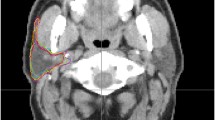

CT images showing different OAR contours Reference contours according to the ICG (lilac) vs delineations from the different RO. a brainstem (sagittal plane): difference in cranial and caudal borders; b oral cavity, spinal cord and PG (axial plane): Inclusion of buccal mucosa (green contour) and teeth (orange and pink contours) by some RO. Variation in spinal cord and PG contours; c spinal cord (sagittal plane): difference in cranial and caudal borders. ICG international consensus guidelines, PG parotid glands, RO radiation oncologist

Two thirds (68%) of the submissions included the oral cavity (70% with ICG vs 66% without). Two RO included the teeth (one used the ICG), and one RO who used the ICG included the buccal mucosa (Fig. 3b). The cranial border was consistently selected as the mucosa of the hard palate, but the posterior and caudal border showed more variation (Additional file 6: Fig. 4g). One RO excluded the posterior part of the tongue, and another the base of tongue.

The parotid glands (PGs) were delineated most often by all RO. Only one right parotid gland was not delineated by one RO for an unknown reason. At the anterior border the masseter and pterygoid muscles were sometimes included and at the medial border the digastric muscle (Fig. 3b + Additional file 6: Fig. 4h). The cranial and caudal borders varied up to a few slices.

There are several reasons that could explain the contour variation between RO and the reference contour in the present study. A reason that has already been mentioned, is that different guidelines are used, either because the ICG [18] were not known to exist, or because other guidelines were used. The effect of using the ICG could clearly be seen on several OARs, namely the cochleas, glottic area, PCMs and supraglottic larynx, which were delineated more often and with better agreement. Figures 1 and 2 support this hypothesis because MSD is significantly smaller for the RO using the ICG compared to the other group (p = 0.008). However, even when the ICG are used, there was still IOV compared to the reference contours. A first possible reason is that the edges of the OARs may be unclear/blurry on CT (PCMs, anterior and medial borders of PGs), needing interpretation by the delineating RO, which can result in IOV. Secondly, different CT windowing can also have an impact on OAR visualisation, resulting in different volumes. Thirdly, the guidelines might be misunderstood or misinterpreted. For example the supraglottic larynx which should start cranially at the tip of the epiglottis was delineated by one RO including the air surrounding the tip (Additional file 6: Fig. 4n). The inclusion of air has a large impact on the volume delineated, which is also often seen in case of the oral cavity. Another misinterpretation occurs at the cranial and caudal borders, which often differed a few slices. For example at the caudal border of the brainstem, because the “tip of the dens of C2” can be prone to misinterpretation (Fig. 3a). Also the spinal cord showed variation in the caudal border because some RO delineated it all the way to the most caudal slice of the CT, and others stopped more cranially. Two RO who used the ICG delineated the spinal canal instead of the spinal cord so these were excluded from the analysis which resulted in less delineations (Table 1) and less agreement (Fig. 2). Not only the delineated volumes differed, but also whether the OAR was delineated or not varied significantly. The mandible, brainstem, spinal cord, salivary glands and oral cavity were consistently delineated in all patients, irrespective of which RO delineated them. But several OARs seem less well-known, especially to RO who did not use the ICG. This resulted in less than half of them to delineate the cochleas, glottic area, PCMs and supraglottic larynx. Even the RO using the ICG did not always delineate the OARs described in the guidelines, even though they did delineate them more often (Table 1). A reason for this could be that the RO may have deemed delineation of the OAR unnecessary for treatment planning because the tumour was situated far away or too close to spare the OAR anyway.